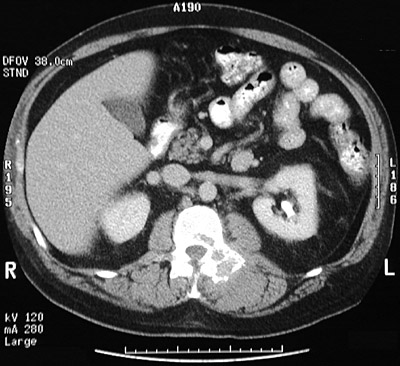

| The destructive, expansile lytic lesion seen above involving the L2 vertebral pedicle on the left with an abdominal CT scan is a solitary plasmacytoma. A closer CT view is shown below. In this case, there was no increase in serum IgG and no monoclonal "spike" on either serum or urine protein electrophoresis. |